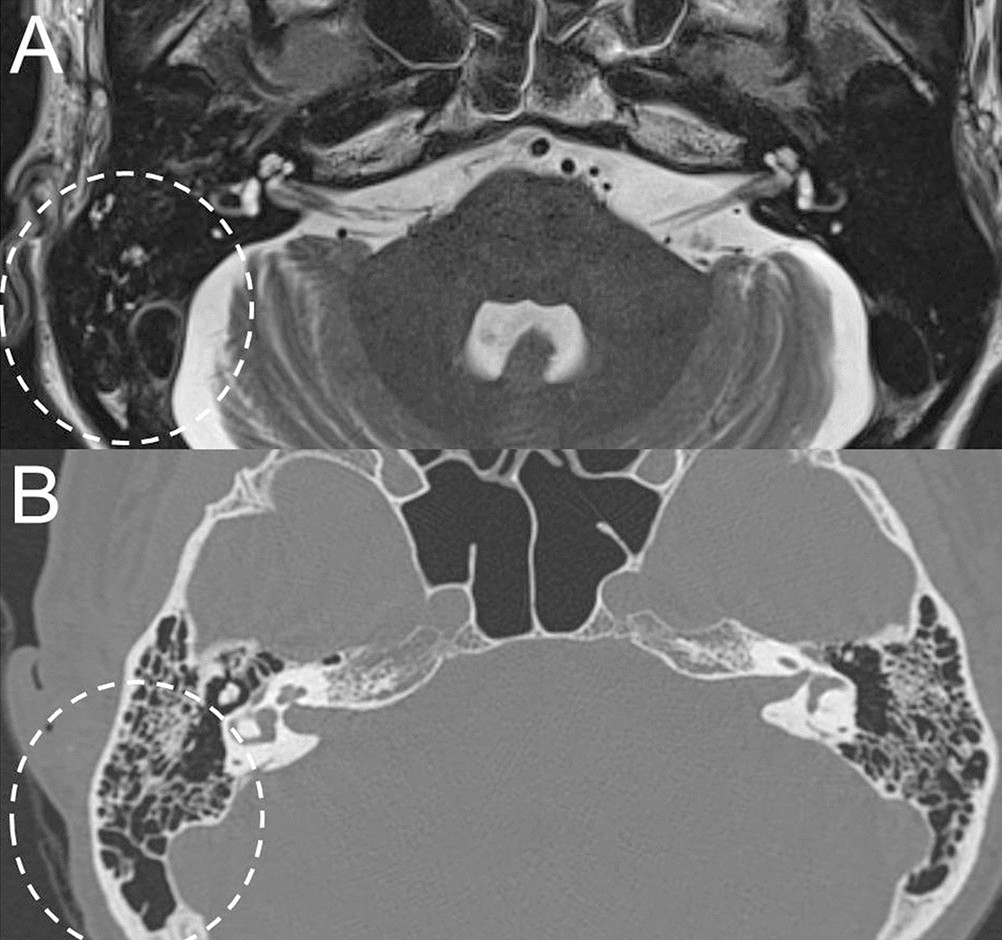

Figure 4

From: Mastoid effusion on temporal bone MRI in patients with Bell’s palsy and Ramsay Hunt syndrome

Comparison between temporal bone MRI and TBCT in a representative case of Ramsay Hunt syndrome with mastoid effusion on the right side. Non-contrast axial T2-weighted image at the level of IAC and mastoid air cells shows high signal intensity from the fluid in the right mastoid suggesting mastoid effusion (dotted circle, A), which was not easily identifiable in TBCT (dotted circle, B).